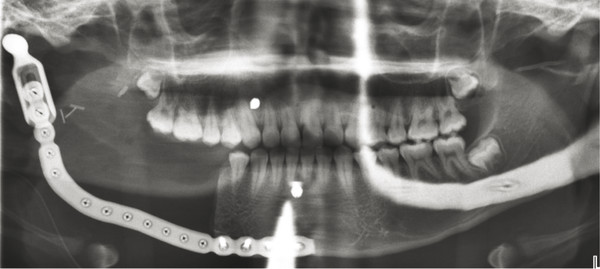

Another similar radiographic presentation to a traumatic bone cyst is the aneurysmal bone cyst (ABC). This lesion tends to favor the female population, and often, there can be jaw swelling and pain. The most common type is the vascular type, which can be rapid growing and destructive (Fig. 9‑4a, b). Unlike a traumatic bone cyst, on entry of this lesion, you will encounter brisk bleeding, which is controllable with pressure and resolves with curettage of the lesion (Fig. 9‑4c–e). Aneurysmal bone cysts tend to have a recurrence rate of 10% and are part of a spectrum of vascular lesions; these cysts are associated with jaw tumors.